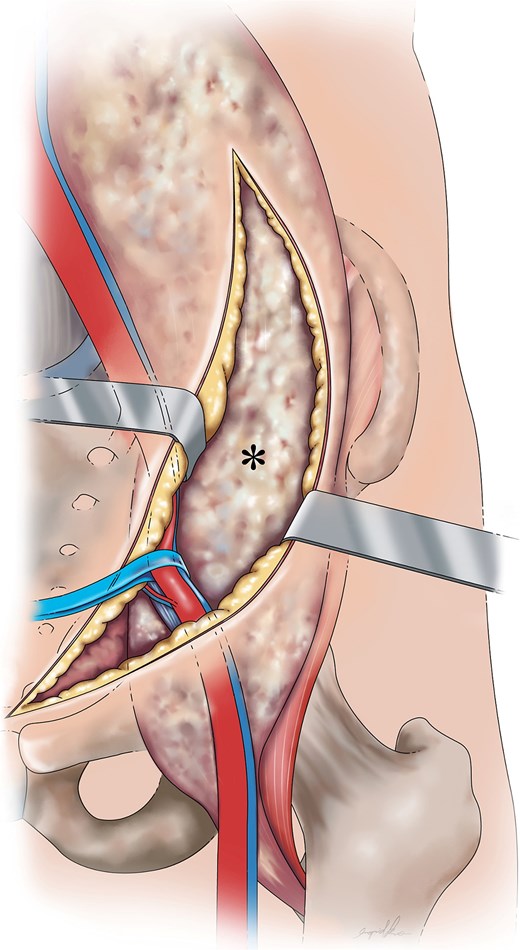

The surgery consisted of two stages: the pararectus approach for the psoas abscess and the modified Hardinge approach for the hip joint. During the pararectus approach, the involved iliacus psoas was detected by blunt dissection after surgical dissection, deepening into the external abdominal aponeurosis (Fig. 3). Approximately 400 ml of purulent fluid was drained. After confirming that there was no retained lobulated abscess within the retroperitoneum, the surgical wound was closed in layers, and two Jackson-Pratt drains were inserted. Following this procedure, the hip lesion was treated as scheduled.

Graphical depiction of a psoas abscess (*) following dissection from the abdominal wall, fascia layers (Camper’s and Scarpa’s fascia), external oblique aponeurosis, and transversalis fascia with medial retraction of the external iliac vessels.